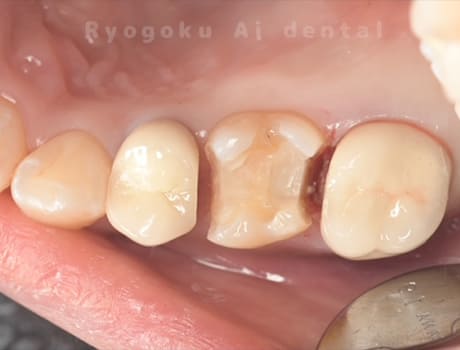

- 重度カリエス

-

- 治療内容

- マイクロエンド

- 治療費用

- 99,000円

- 担当医

- Dr. 炭野

虫歯が大きく、神経の保存ができなかったため、マイクロエンド治療を行いました。